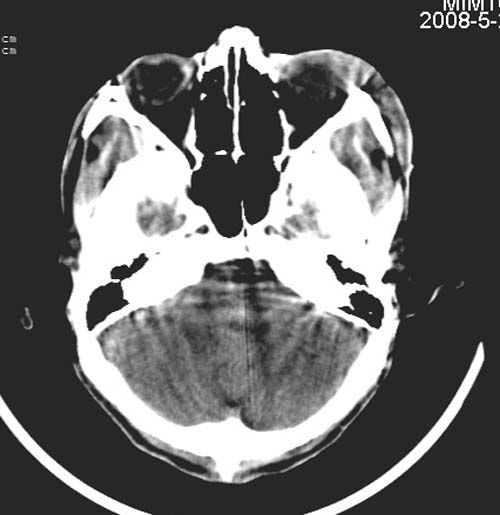

患者,男,26岁。头面部外伤半小时。

左额部软组织损伤,左泪囊损伤

复查一下吧,左侧颞叶两个层面都有异常密度灶。不知道是伪影不。

左侧眶部软组织肿胀,楼主是不是考虑有静脉窦血栓?复查或增强扫描。

左侧眶部软组织肿胀,楼复查或增强扫描。